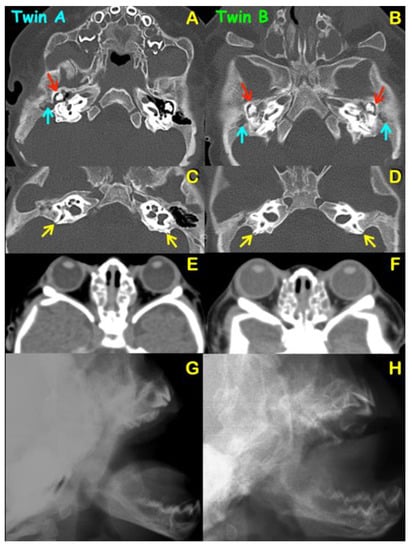

2. Patient Report

4.3. Malformation of Middle Ear and Hearing Loss

4.4. Dehiscence of Posterior Semicircular Canals

3.2. Hearing Assessment